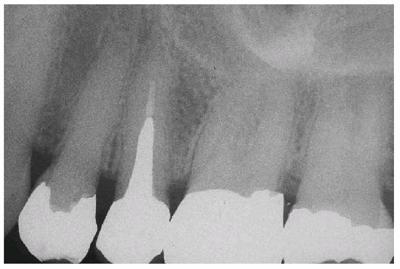

the amalgam-tooth interface (Figur 323s1823d es 18-12A 18-12B 18-12C 18-12D 18-12E, and 18-12F

Figur 323s1823d e 18-12A: Periapical radiograph showing tooth #30 after successful root canal treatment.

Figur 323s1823d e 18-12B: Bitewing radiograph showing tooth #30 with amalgam core build-up completed. Note that the core material extends approximately 2 mm into the canal orifices for increased retention.